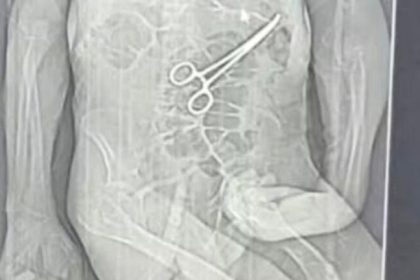

Idoso morre após pinça ser deixada no corpo em cirurgia

A família de Manoel Cardoso de Brito, de 68 anos, acusa o Hospital Municipal…